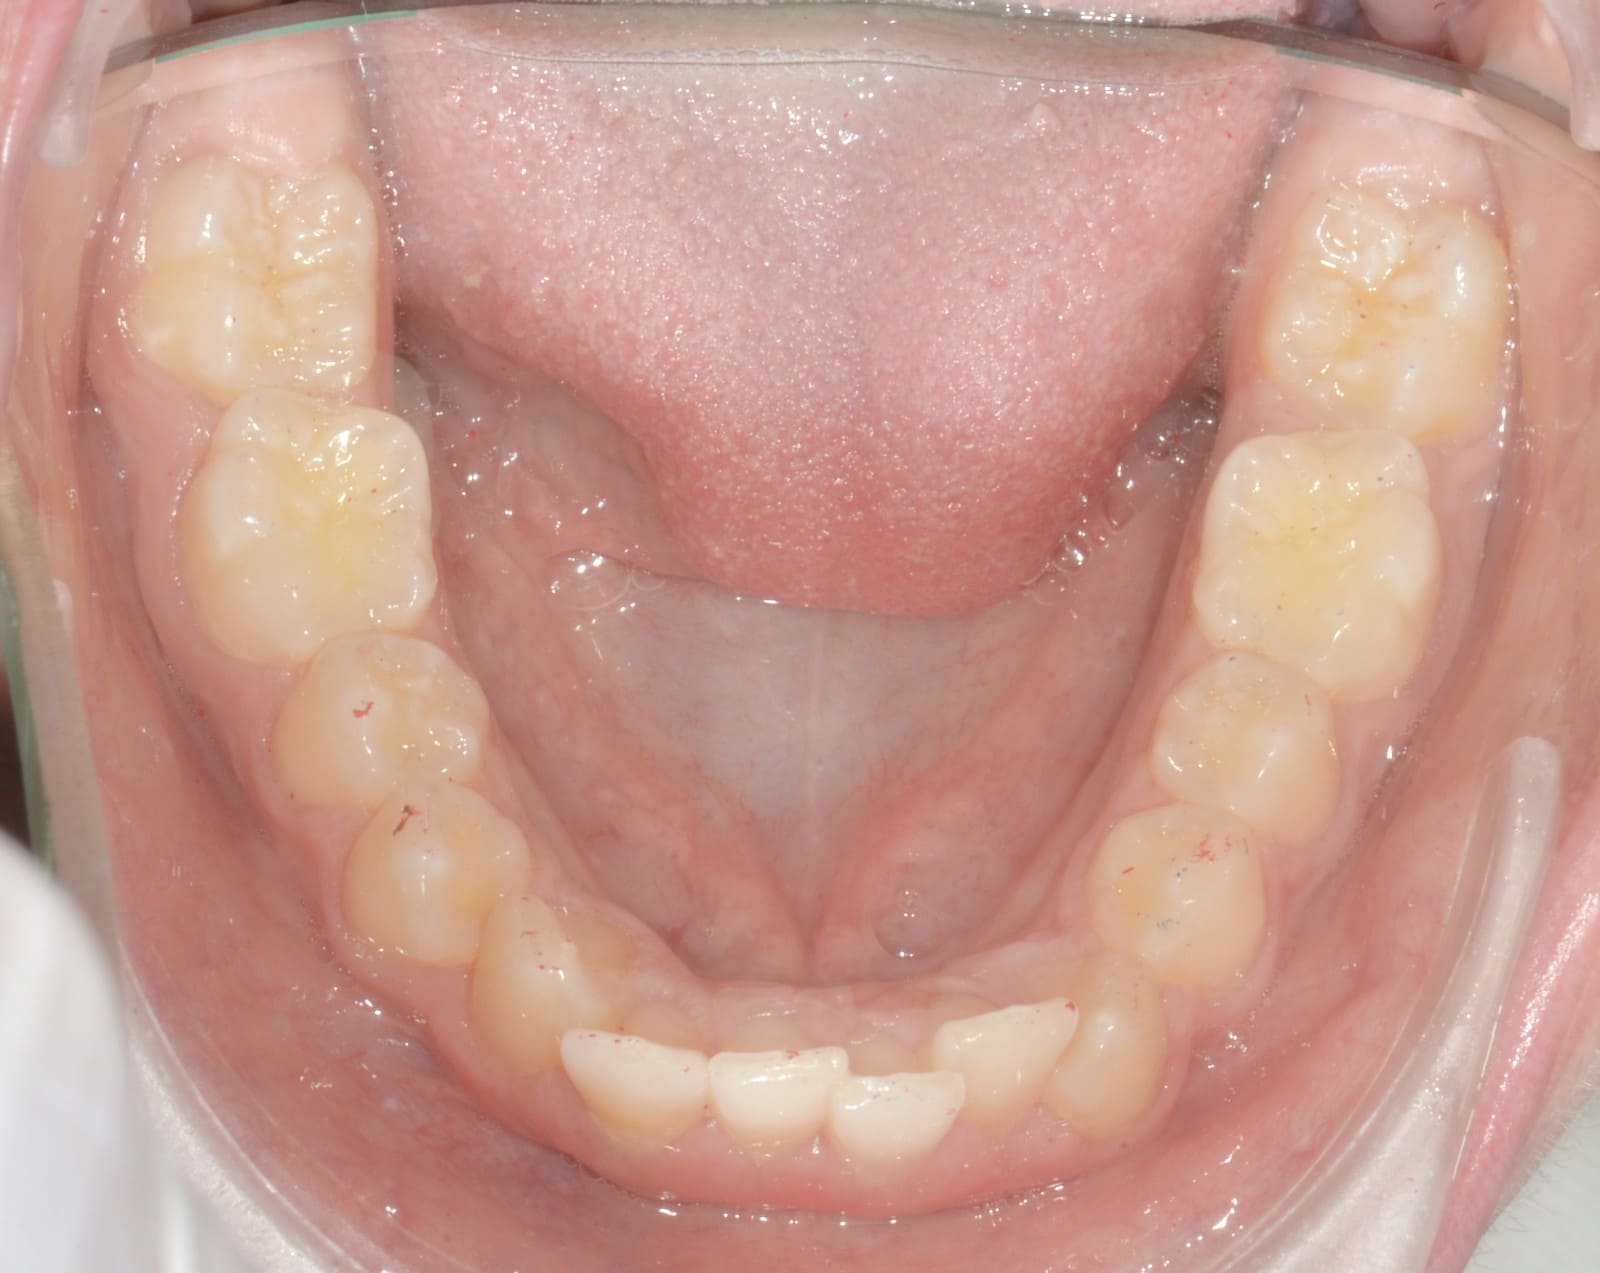

Initial